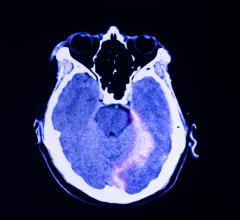

September 20, 2022 — Children and adolescents who have either recovered from COVID-19 or have long COVID show persistent ...